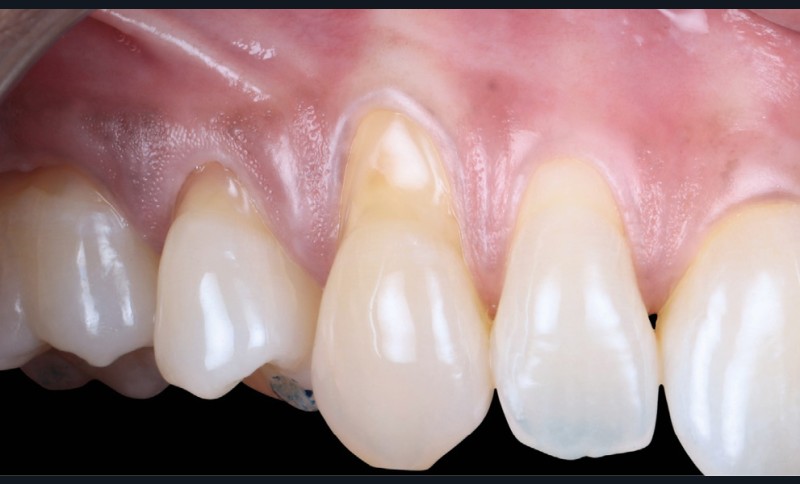

- secteur 1 : papilles étroites et rétruses (fig. 2) ➠ technique de tunnellisation ;